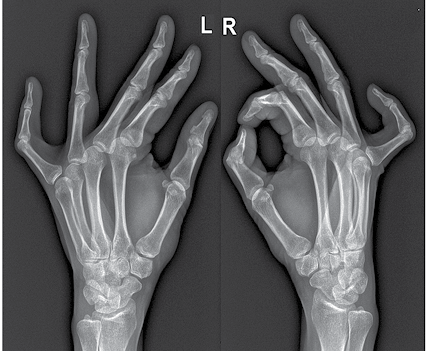

4 pav. Pacientės plaštakos (matyti abiejų rankų penktųjų pirštų kontraktūra)

6 pav. Pacientės plaštakos iš priekio

7 pav. Pacientės plaštakų rentgeno nuotrauka